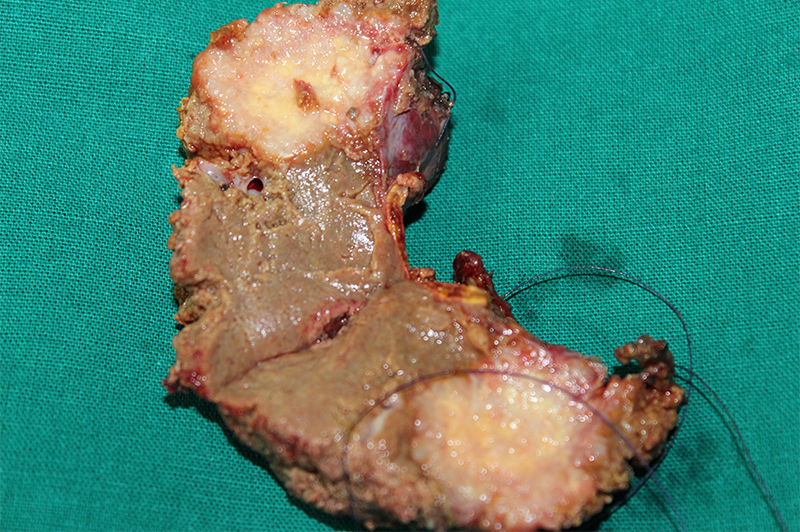

45 year old gentleman was diagnosed with right colon cancer (poorly differentiated adenocarcinoma) and solitary metastasis to liver. He underwent a one stage surgery (right hemicolectomy for colon cancer and resection of liver metastasis). The surgery was followed by multiple cycles of chemotherapy. A chemoport was placed for the same. The patient lived for 4 years after diagnosis of advanced poorly differentiated colon cancer.

Patients who have a localized disease undergo a curative colonic resection (right or left hemicolectomy / sigmoid colectomy / anterior resection depending on which part of colon involved ). The surgery is performed as an open or laparoscopic surgery depending on the expertise available, extent of nodal disease and surrounding organ involvement / the bulkiness of tumor and patient presentation. Patients presenting with intestinal obstruction may need an emergency surgery, which may end in doing an ileostomy / colostomy (exteriorization of unobstructed part of small intestine or colon as a temporary or permanent measure). Patients presenting with spread disease benefit with initial chemotherapy as mentioned before and it is later followed by a curative surgery where feasible. This is further followed by chemotherapy.